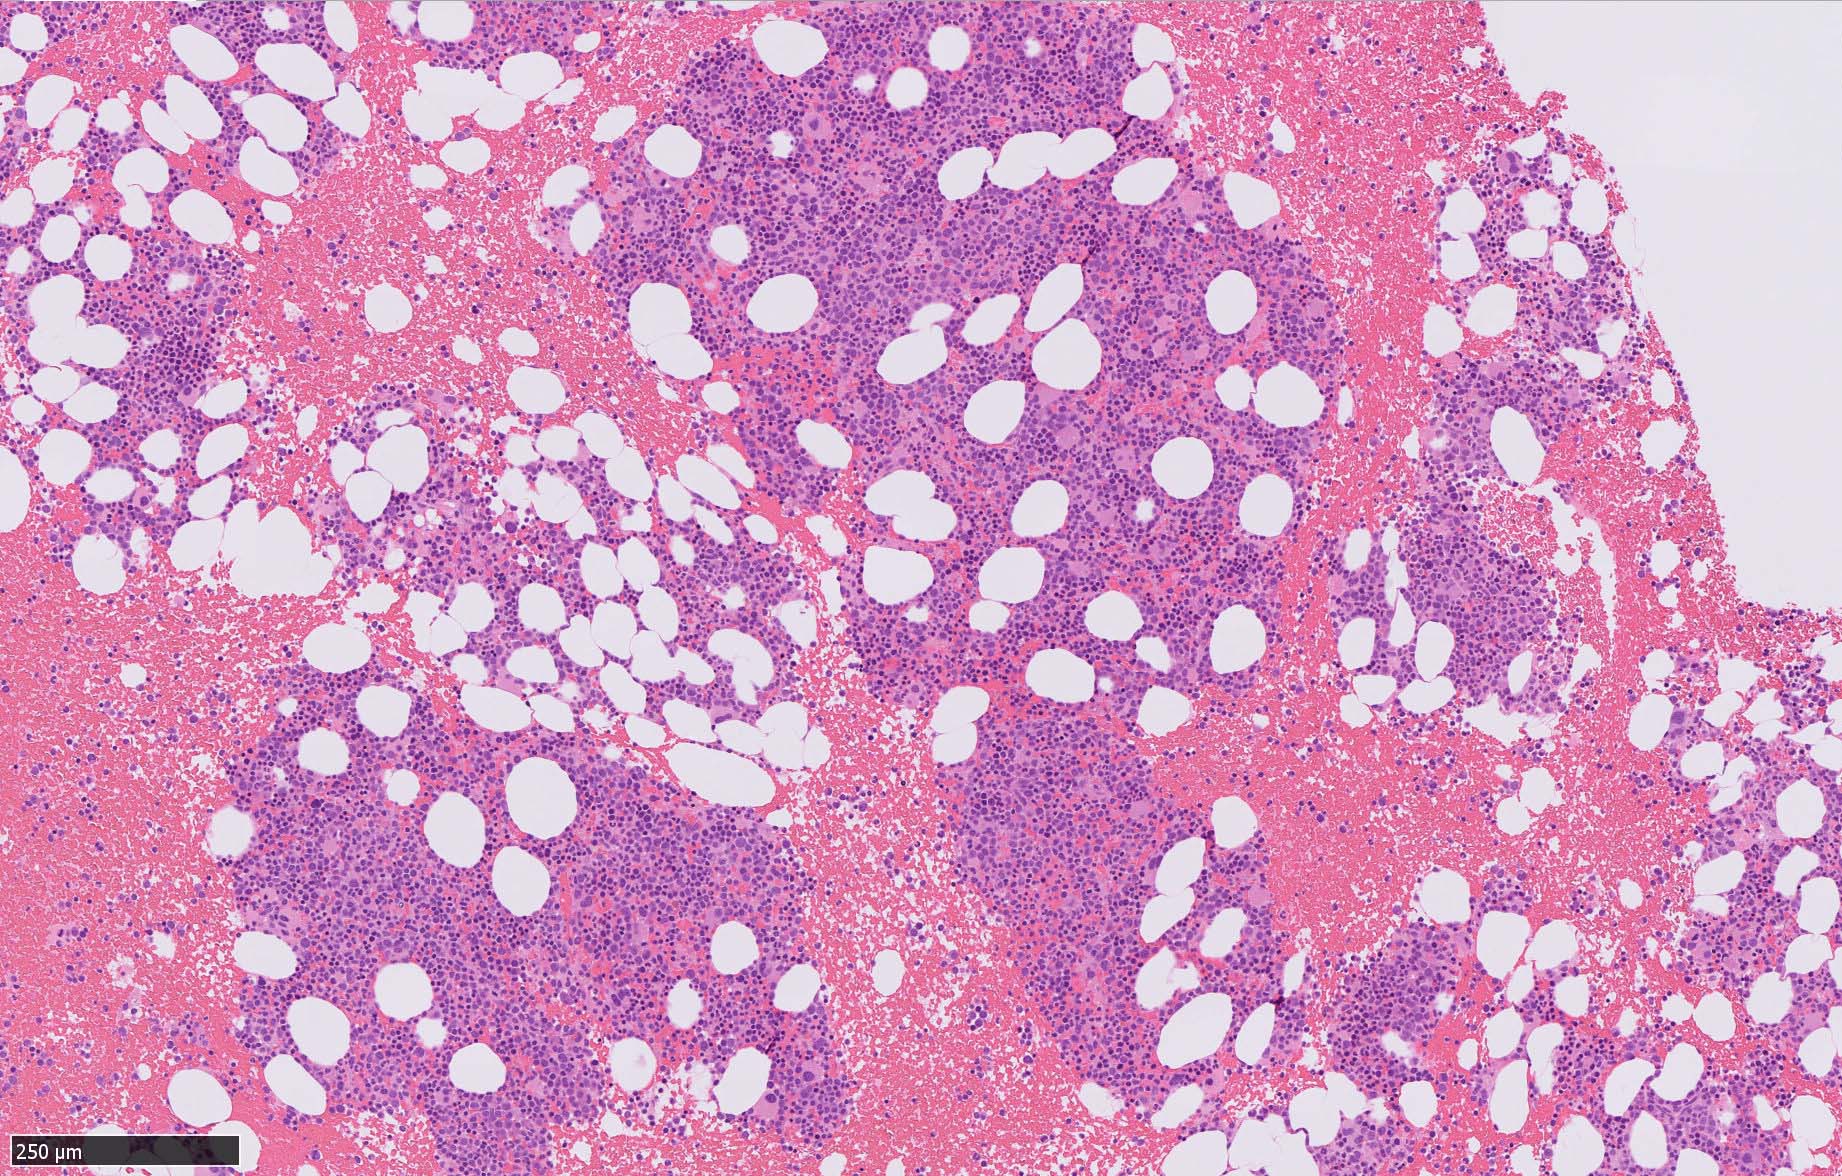

骨髄病理所見

HEでは腫瘍細胞の同定が難しい. 本症例は ASD-Giemsa染色を見ても, 腫瘍胞巣はよくわからなかった. 皮膚が先に診断がつき, 次いでBone marrowだったため, 免疫染色にすすめたが, Bone marrowが先だと診断に困ったかもしれない.

免疫染色

CD4は染まりすぎの感がある(濃く染まる細胞はCD4+ T-cellかもしれない). CD56, CD123が陽性で可能性が高くなり, BPDCNの診断にはCD34は陰性であることが必要

TCF4、CD123、TCL1をconsultationにより染色していただき, 陽性を確認した. CD34-, lysozyme-, CD123(おいてある病院は少ないかも)をしらべて, BPDCN研究会あてconsultationをする流れでしょうか.